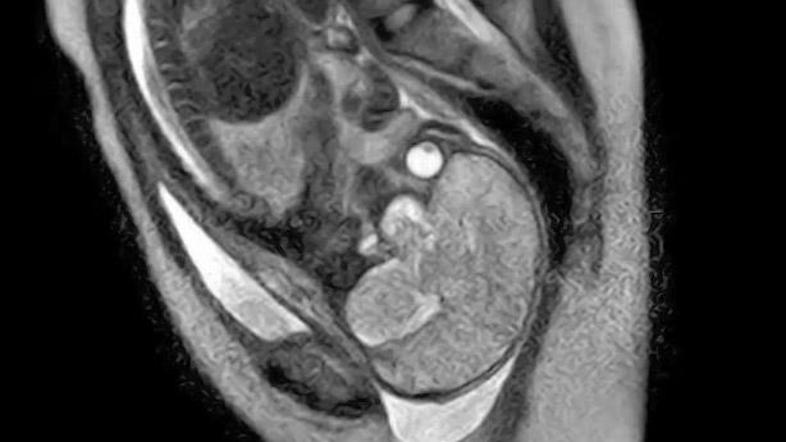

Nemški zdravniki so z magnetno resonanco fotografirali rojevanje otroka. Kot so dejali v berlinski porodnišnici, bodo s fotografijami imeli lažjo predstavo o morebitnih zapletih pri rojstvih otrok.

"Glavni razlog za raziskovanje je odgovoriti na vprašanje, zakaj se lahko zgodijo zapleti pri porodu in da s sliko zajamemo proces rojevanja in morebitne komplikacije," je dejal vodja raziskovalne ekipe Christian Bamberg.

"Fotografije so spektakularne," je dejal Bamberg. "Prikazujejo, kako se še nerojen otrok premika v porodnem kanalu, kako se premaknejo njegove kosti in kako njegova glavica spremeni smer."

Fotografije rojstva so bile posnete 20. novembra, celotno snemanje pa je trajalo eno uro.